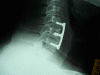

The fusion rate represents one of the most commonly used criteria for evaluating the efficacy of spinal surgical techniques and the effectiveness of newly developed instrumentation and spinal implants. Reported fusion rates are not frequently supported by adequate information regarding by whom and how fusion was defined. In our prospective study we examined the fusion rate in patients undergoing first time anterior cervical discectomy and fusion for degenerative disease. Separate, well-defined radiographic fusion criteria were used and the 12-month post-operative X-rays were reviewed independently by a neurosurgeon, a neuroradiologist and an orthopedic surgeon, who were not involved in the patients' management. The observed fusion rates were 77.3, 87.8 and 84.7% respectively. Statistical analysis demonstrated concordance rates of 87.8, 91 and 91.4% and Kappa coefficients of 0.585, 0.620 and 0.723 for each pair of evaluators. Another set of ratings of the same radiographs, by the same interviewers, was obtained 6 weeks after the initial one. The reported fusion rates were 78.2% for the neurosurgeon, 87.4% for the orthopedic surgeon, and 86.1% for the neuroradiologist. Statistical analysis demonstrated intra-observer concordance rates of 98.7, 92.2 and 97.9% respectively, while the Kappa coefficients were 0.963, 0.677 and 0.907 for each reviewer. Our findings confirm the necessity of defining and describing criteria for fusion whenever this rate is reported in clinical series. The lack of widely accepted, well-defined criteria makes comparison of these results difficult. The development of a well organized, prospective clinical study in which fusion and outcome will be assessed by both clinical and radiographic parameters could significantly contribute to a more accurate evaluation of overall outcome of cervical spinal procedures.